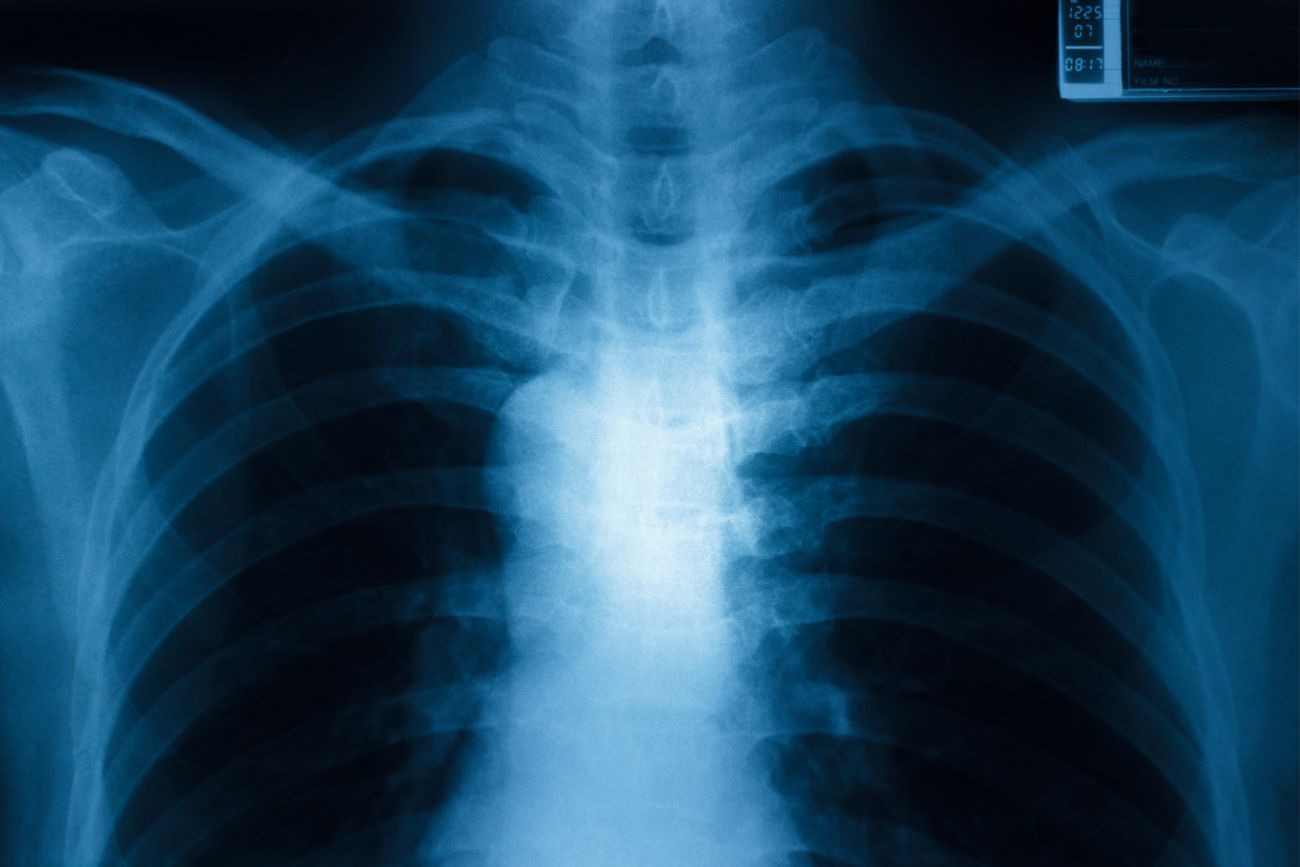

En ese sentido, una radiografía de tórax es a menudo la primera prueba que su médico pedirá para saber si existen una anomalía en los pulmones. Los estudios por imágenes se pueden hacer por varias razones tanto antes como después del diagnóstico de cáncer de pulmón.

En cuanto a la radiografía de tórax, no hay datos científicos que avalen hoy que su indicación reduzca la mortalidad por cáncer de pulmón como estrategia de detección precoz.